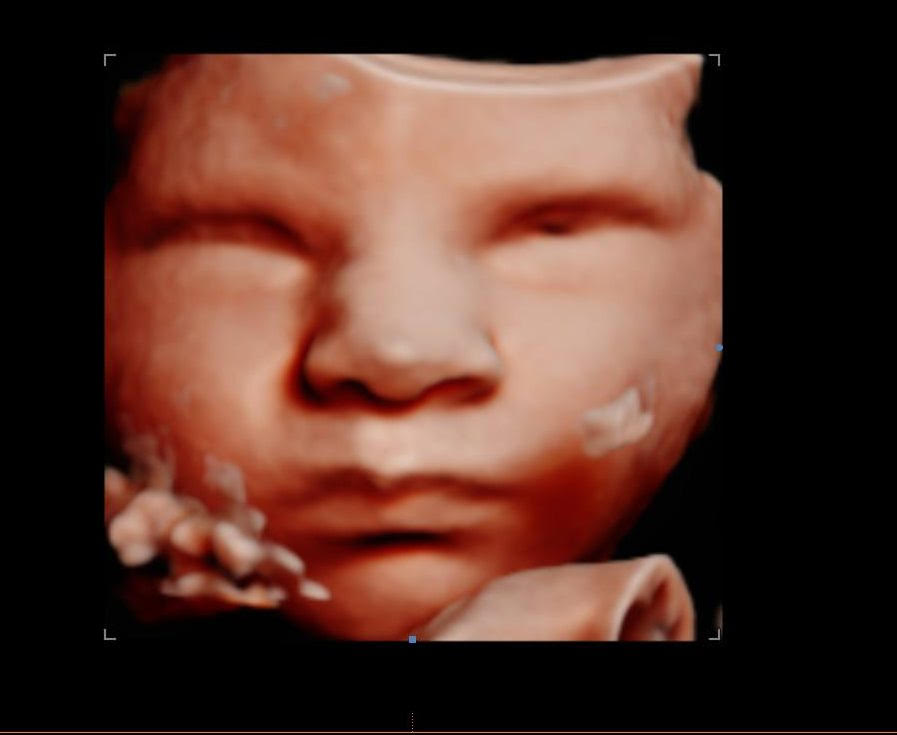

Browsing our 4D ultrasound photos gives you a clear idea of what your session can look like. You will see a range of images, from early 2D visits and gender reveal moments to rich 3D, 4D, and HD live facial detail captured during the most popular weeks between 26 and 32 weeks. Babies are unpredictable, but we have spent many sessions helping families get those sweet expressions, tiny stretched arms, and peaceful faces that you will want to hold onto for years.

Your session at Behind the Bump HD begins with your comfort. We start with 2D imaging to locate baby and find the best viewing angle, then move into 3D, 4D, and HD live ultrasound when position allows. Most visits last between 10 and 25 minutes of scanning time depending on your chosen package, and we take the time to try different positions and techniques to capture the clearest possible views.

Image clarity depends on factors like baby’s position, amniotic fluid levels, and gestational age. If your heart is set on detailed facial images, booking between 26 and 32 weeks gives you the best chance of seeing those fuller features and that characteristic stillness babies often have later in pregnancy.